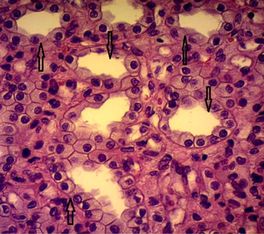

Рис. 27. Собирательные трубочки в мозговой зоне почки американской норки

Рисунок 27 – Собирательные трубочки в мозговой зоне почки американской норки. Окраска гематоксилином и эозином. Объектив ×40, окуляр ×10 (Распутина О.В., 2023)